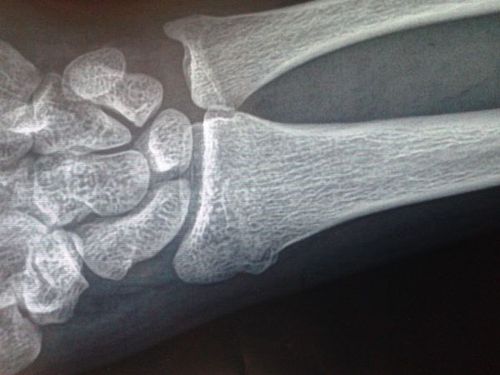

手腕舟骨 div c

陈旧性右腕骨骨折

手腕骨裂

骨裂的片子图片

骨裂x片